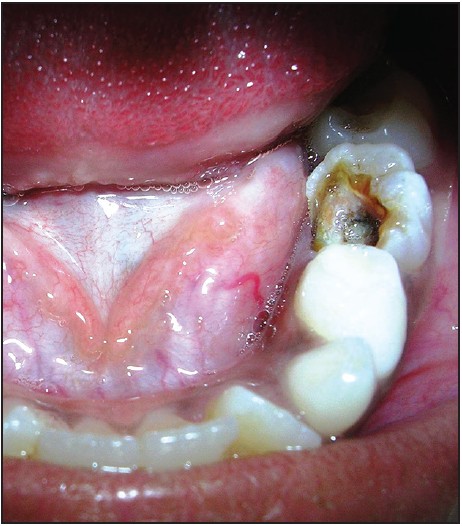

पेशंटच्या आई वडिलांचा असा गैरसमज होण्याचं कारण असं की, आपल्या तोंडातली पहिली पक्की दाढ ही वयाच्या सहाव्या वर्षीच, सर्व दुधाच्या दातांच्या मागे हजेरी लावते. कुठलीही दुधाची दाढ न पडता ही दाढ येते .

त्यामुळे बऱ्याचदा ती आल्याचं आई-वडिलांच्या लक्षात येत नाही. त्यामुळे ती किडली असं दिसलं तरी दुधाचेच दात आहेत, पडेल…. म्हणून दुर्लक्ष केलं जातं किंवा अलीकडच्या दुधाच्या दाताच्या कॅव्हिटी मध्ये जेवण अडकून ही मागची पक्की दाढसुद्धा कधी कधी खराब होते (सुक्याबरोबर ओलं जळतं तसं)

दुधाच्या दाढा पडून त्यांच्या जागी उपदाढा किंवा छोट्या दाढा येतात. मात्र वयाच्या सहाव्या वर्षी पहिली पक्की दाढ आणि बाराव्या वर्षी दुसरी पक्की दाढ येते ;सर्व दुधाच्या दाढांच्या मागे… अलीकडच्या दुधाच्या दाढा जर अजून पडायच्या असतील तर एक्स-रे मध्ये त्याखाली येण्यासाठी तयार असलेली पक्की दाढ सुद्धा दिसते पण पक्क्या दाढेच्या खाली अशी कुठलीच दाढ नसते; हे आम्ही दाखवतो .

हे टाळण्यासाठी खरं म्हणजे लहान वयापासूनच मुलांचे दर सहा महिन्यांनी दातांचे चेकअप करून घेणे गरजेचे असते ; म्हणजे दुधाच्या दातांमधल्याही कॅव्हिटी लवकर ओळखता येतात .त्यांचा लवकर इलाज करता येतो. नवीन आलेल्या पक्क्या दाढांना देखील कॅव्हिटी होण्याआधीच ; खबरदारी म्हणून ” सील ” करता येते.